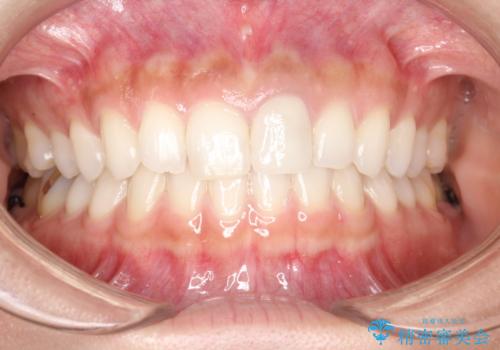

前歯のかぶせ物の色があっていない オールセラミック治療

- 以前装着された前歯のかぶせ物の色を変えたいとのことで来院されました。

土台からの再治療を行い、オールセラミッククラウンを装着する治療計画としました。

保険適用のかぶせ物は天然の歯のような色見を表現するのは難しいといえます。

自然な歯をご希望な場合、金属を使わないオールセラミックがおすすめです。